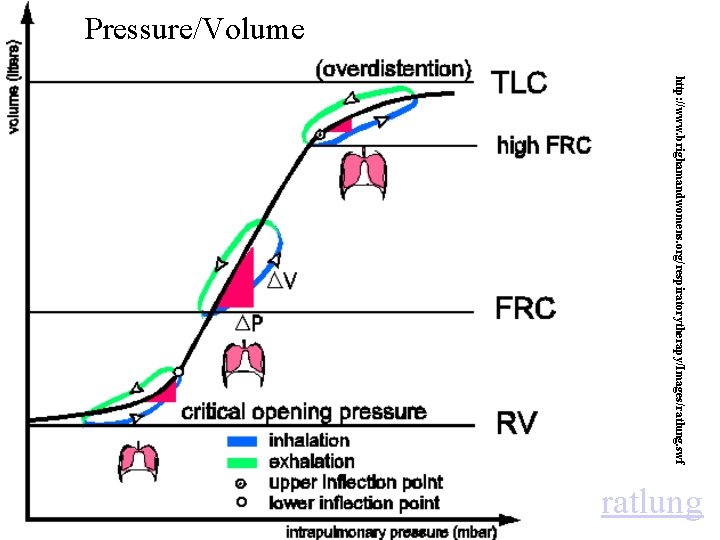

Pressure/Volume http: //www. brighamandwomens. org/respiratorytherapy/Images/ratlung. swf ratlung